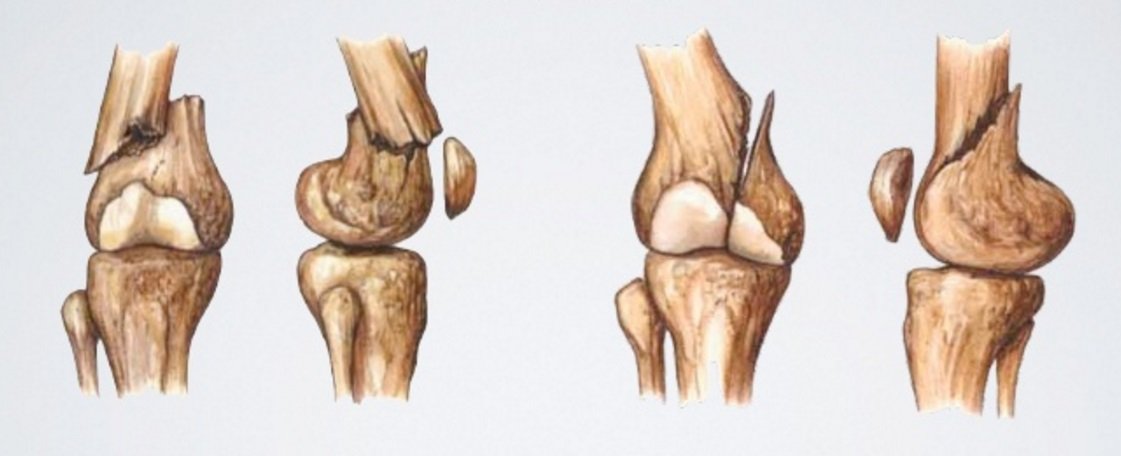

Такая опасная травма мыщелка большеберцовой кости представляет собой тяжёлое внутрисуставное повреждение тканей проксимального эпифиза, сопровождаемая нарушением целостности поверхности сочленения. Появляется она в ходе сильного и прямого удара по колену или в результате неудачного падения с высоты на вытянутые ноги, в результате дорожно-транспортного происшествия. А также привести к такому повреждению и значительно повысить вероятность его появления может такой негативный сопутствующий фактор, как развитие остеопороза.

Основные симптомы перелома мыщелка

В каждом отдельном случае точные симптомы и степень их интенсивности у человека проявляется по-разному в зависимости от степени тяжести травмы, общего состояния здоровья и иных особенностей ситуации. Тем не менее обращаться за помощью к специалистам следует при появлении следующих симптомов:

- Сильная и резкая боль в области колена.

- Появление отёчности в области повреждения.

- Отсутствие возможности совершать движения нижней конечностью.

- Деформация голени вбок при смещении отломка кости.

- При открытом переломе наблюдается выступание отломков кости через рану с кровоподтёками.

- Появление гемартроза, представляющего собой разрыв сосудов с кровоизлияниями в повреждённый сустав.

- Ненормальная подвижность «плавающего» надколенника.